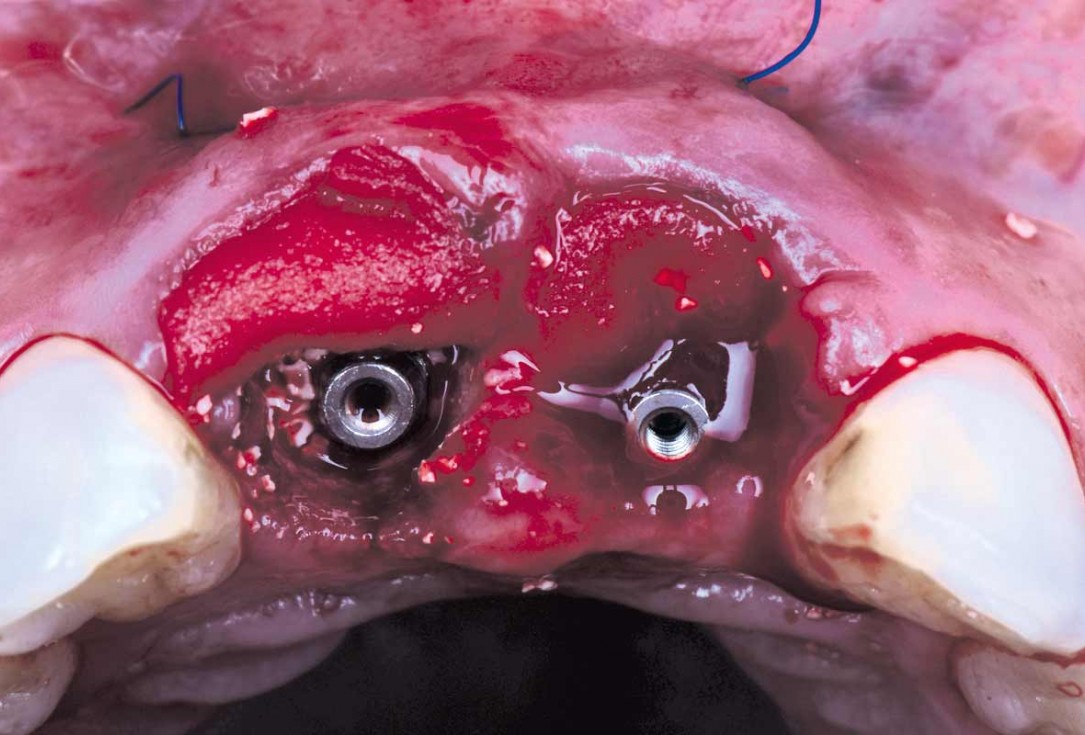

09/22 - Gap is filled with cerabone®cerabone® and mucoderm® for immediate implantation in the aesthetic area - Dr. D. Robles